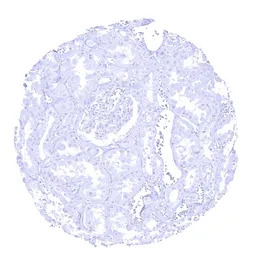

IHC-P analysis of human kidney tissue section using GTX04445 Elastase 3B antibody [MSVA-410M] HistoMAX.

Elastase 3B immunostaining is absent in kidney tissue.